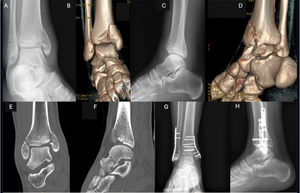

In SAD-2, where there is an associated vertical fracture of the medial malleolus, a CT scan is recommended to rule out joint impaction of the internal column, which can occur in 61–73% of cases.18,24 In this type of fracture, surgical treatment of both malleoli is required. For fixation of the medial column, it is recommended to follow the same principles as for treatment of a tibial pilon, using a medial plate to improve biomechanical support, and to restore joint collapse18,25 (Fig. 3).

(A–D) Example of transverse fracture of the infrasyndesmotic fibula SAD-2 with vertical line in the internal column. (E and F) CT image showing medial impaction and articular cartilage collapse. (G and H) Postoperative X-rays showing osteosynthesis using anatomical fibula plate, anti-glide plate in internal column, K-wire, and lag screw to restore the articular surface.